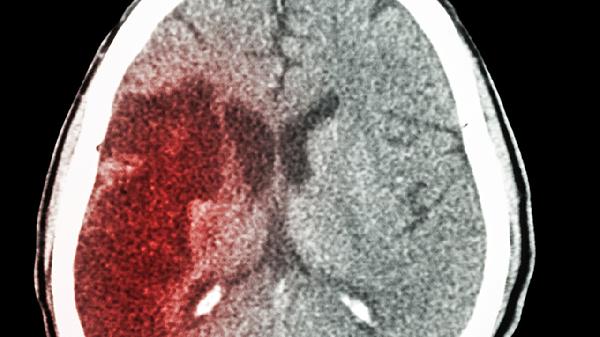

脑梗后视力下降可通过视觉训练、药物治疗、手术治疗、中医调理和营养干预等方式恢复。脑梗视力下降通常由视神经损伤、视网膜缺血、脑部视觉中枢受损等因素引起。